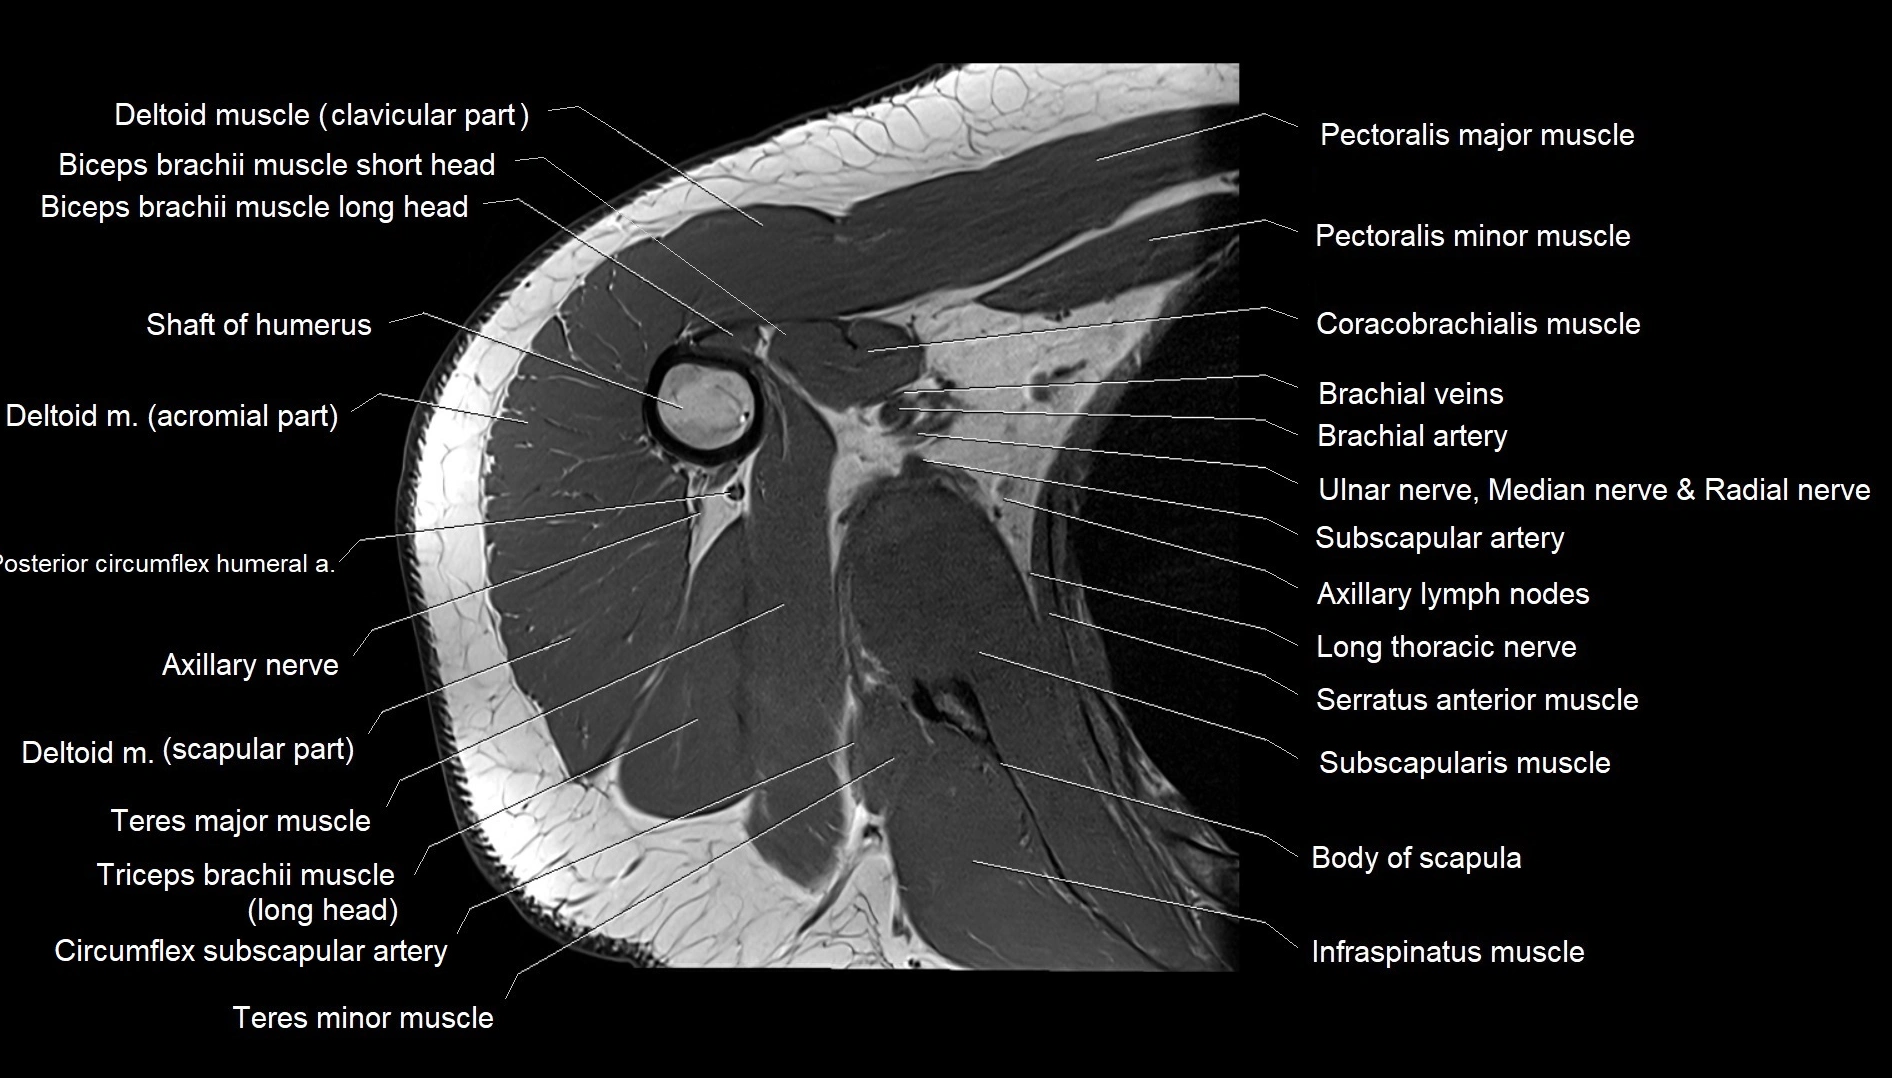

MRI images

image